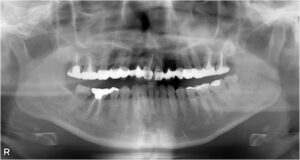

上顎前歯1本欠損症例

BEFORE AFTER 66歳男性/上顎1本欠損/インプラント埋込手術 【治療内容】 右上の前歯は元々ブリッチが入って…